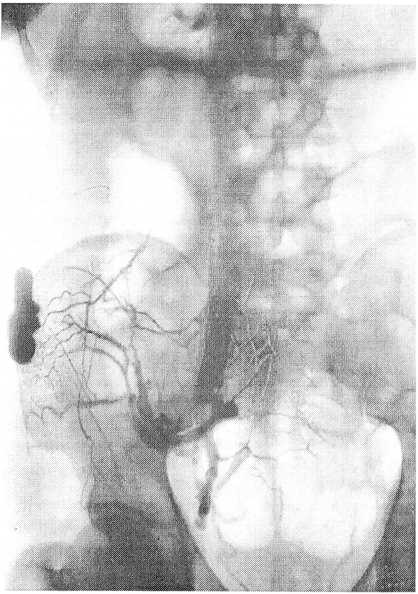

Рис. 1. Рентгенограмма после введения 20 мл контраста

По данным рентгенологических исследований установлено, что рентгеноконтрастная масса введенная даже в небольших количествах (20 мл), немедленно покидает кость. На рентгенограмме (рис. 1) выявлена сеть контрастированных сосудов в области крыла и ямки подвздошной кости, ориентированных к магистральным сосудам таза. При препарировании после введения такого же количества массы Г ероша-Акиловой, она была обнаружена в париетальных венозных стволах крыла и ямки подвздошной кости, в глубокой вене, окружающей подвздошную кость, в пояснично-подвздошной вене, в наружной подвздошной и начальных отделах подчревной вены. При увеличении количества рентгеноконтрастного вещества до 70 мл удалось получить более густую сеть контрастированных сосудов, стали хорошо различимы магистральные сосуды таза, сосудистые сплетения в области крестца, контрастированные сосуды прослеживались и в области малого таза (рис. 2).